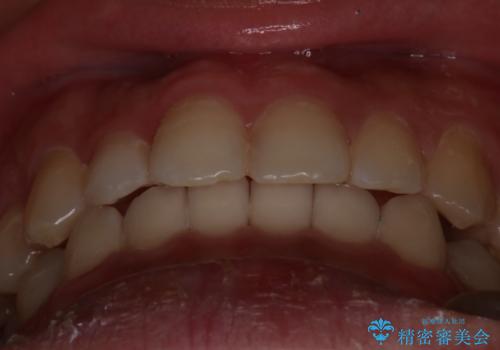

- 前歯のがたつきを主訴に来院されました。初診時、右上2番の口蓋側転位と右下7番の舌側傾斜が認められました。

インビザラインにてIPRと歯列弓拡大を行い、ゴム掛けで噛み合わせを改善する治療計画を立てました。

マウスピースの使用時間が短いため、シュミレーション通り進むか不安でしたが

治療期間1年で、主訴である前歯のがたつきを改善出来、

奥歯の噛み合わせも良くなりました。